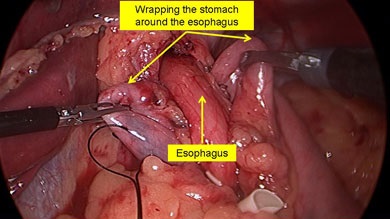

Scopul interventiei chirurgicale este de a restabili bariera antireflux, fără a crea obstacole în calea bolului. Nissen fundoplicatură - chirurgie antireflux, în care folie gastric în jurul părții inferioare a esofagului 360 °. creând o manșetă care previne conținutul gastric în esofag. Inainte de operatie, pacientii ar trebui sa fie examinate cu atenție, o atenție deosebită trebuie acordată la ultimul etaj al radiografiei tractului gastro-intestinal pentru a exclude alte posibile boli.

Principalele etape ale fundoplicatură Nissen:

- mobilizarea fundus gastrice și cardia;

- crearea tunelului din spatele esofagului;

- efectuarea de fundus a stomacului in spatele esofagului;

- creând un drum liber Nissen înălțime manșetă de 1 - 2 cm;

- fixarea manșeta la esofag și piciorul drept al diafragmei;

- excizia sacul herniei și suturarea diafragmei la picioarele HH.

Manșetă Nissen reticulat pe două rânduri sutura.

Realizarea fundus a stomacului in spatele esofagului